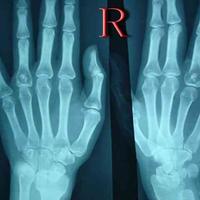

右侧髂骨膨胀性骨质破坏,边缘有硬化,骨皮质不完整,有骨膜反应,可见边缘不清、形态不规则钙化、骨化影。考虑嗜酸性肉芽肿可能。